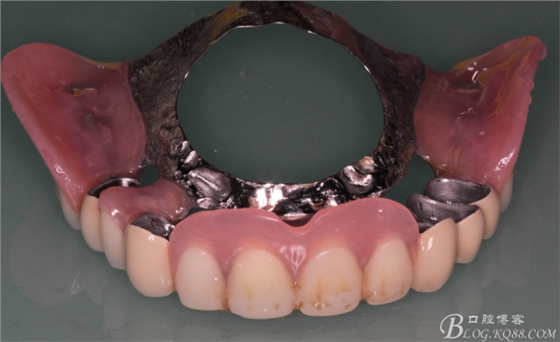

修復(fù)兩年后患者復(fù)診

44作為覆蓋基牙保留完好,牙周狀態(tài)良好,附著體基牙有一定的牙齦萎縮,

上頜套筒冠基牙無(wú)松動(dòng),對(duì)比做牙前得到較大改善

下頜附著體 義齒有菌斑殘留

上頜義齒有煙斑殘留